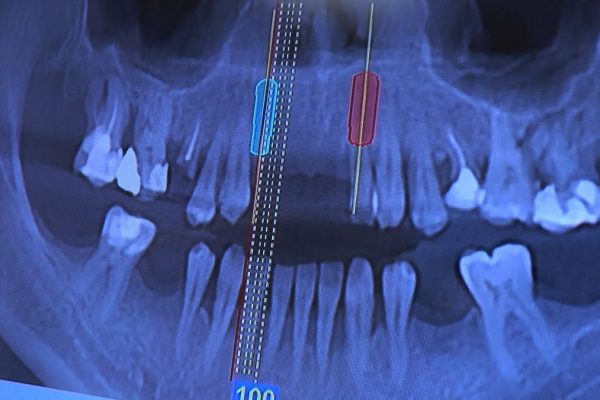

W ostatni weekend czerwca 2018 roku kursanci II Sezonu Preludium Implantologii odbyli piątą, finałową sesję, która w całości podporządkowana była praktyce. W ciągu dwóch dni zabiegowych Lekarze uczestniczący w szkoleniu przeprowadzili szereg zabiegów pod kierunkiem dr n.med. Violetty Szycik. Wszczepili 17 implantów oraz przeprowadzili ekstrakcje i zabiegi regeneracyjne kości. Zabiegi były wykonywane także w sedacji dożylnej z udziałem specjalisty anestezjologii i intensywnej terapii dr Jolanty Grzybowskiej. Preludium implantologii to nowy program edukacyjny dla adeptów implantologii stomatologicznej, którego celem jest wprowadzenie do implantologii poprzez pozyskanie wiedzy w szerokim zakresie i uwzględnieniem szczegółów mających decydujące znaczenie dla powodzenia leczenia implantologicznego. Ale tak jak wszystkie szkolenia w Instytucie Vivadental, w tym wiodące Practiculum Implantologii, zorientowane jest na praktyce i samodzielnym wykonywaniu zabiegów pod kierunkiem Mentora. To najlepsza edukacja w medycynie zabiegowej, a zarazem najlepszy start do implantologii.